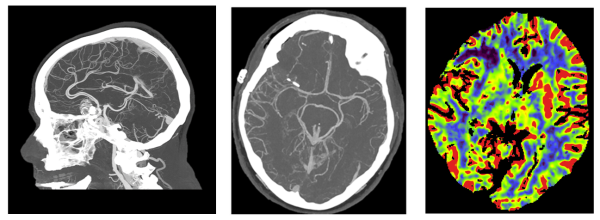

名古屋市立大学大学院医学研究科 放射線医学分野 樋渡昭雄教授は、「NAEOTOM Alpha が持つ高い空間分解能は、血管系の描出、動脈瘤の詳細な解析、動脈解離の評価といったものに非常に役に立つと考えております。CTによる血管撮影で詳細な評価を行う事が出来れば、カテーテルを用いた診断の血管撮影が省略できる可能性があるのではないかと期待しております。また、仮想単色X線、ヨードマップ等のスペクトラルイメージングを活用し、理想的には抗癌剤の分布等も分かれば、臨床的に非常に有用ではないかと思います。」と述べている。

脳梗塞を確認するための血流画像(右) エラスムスメディカルセンター提供